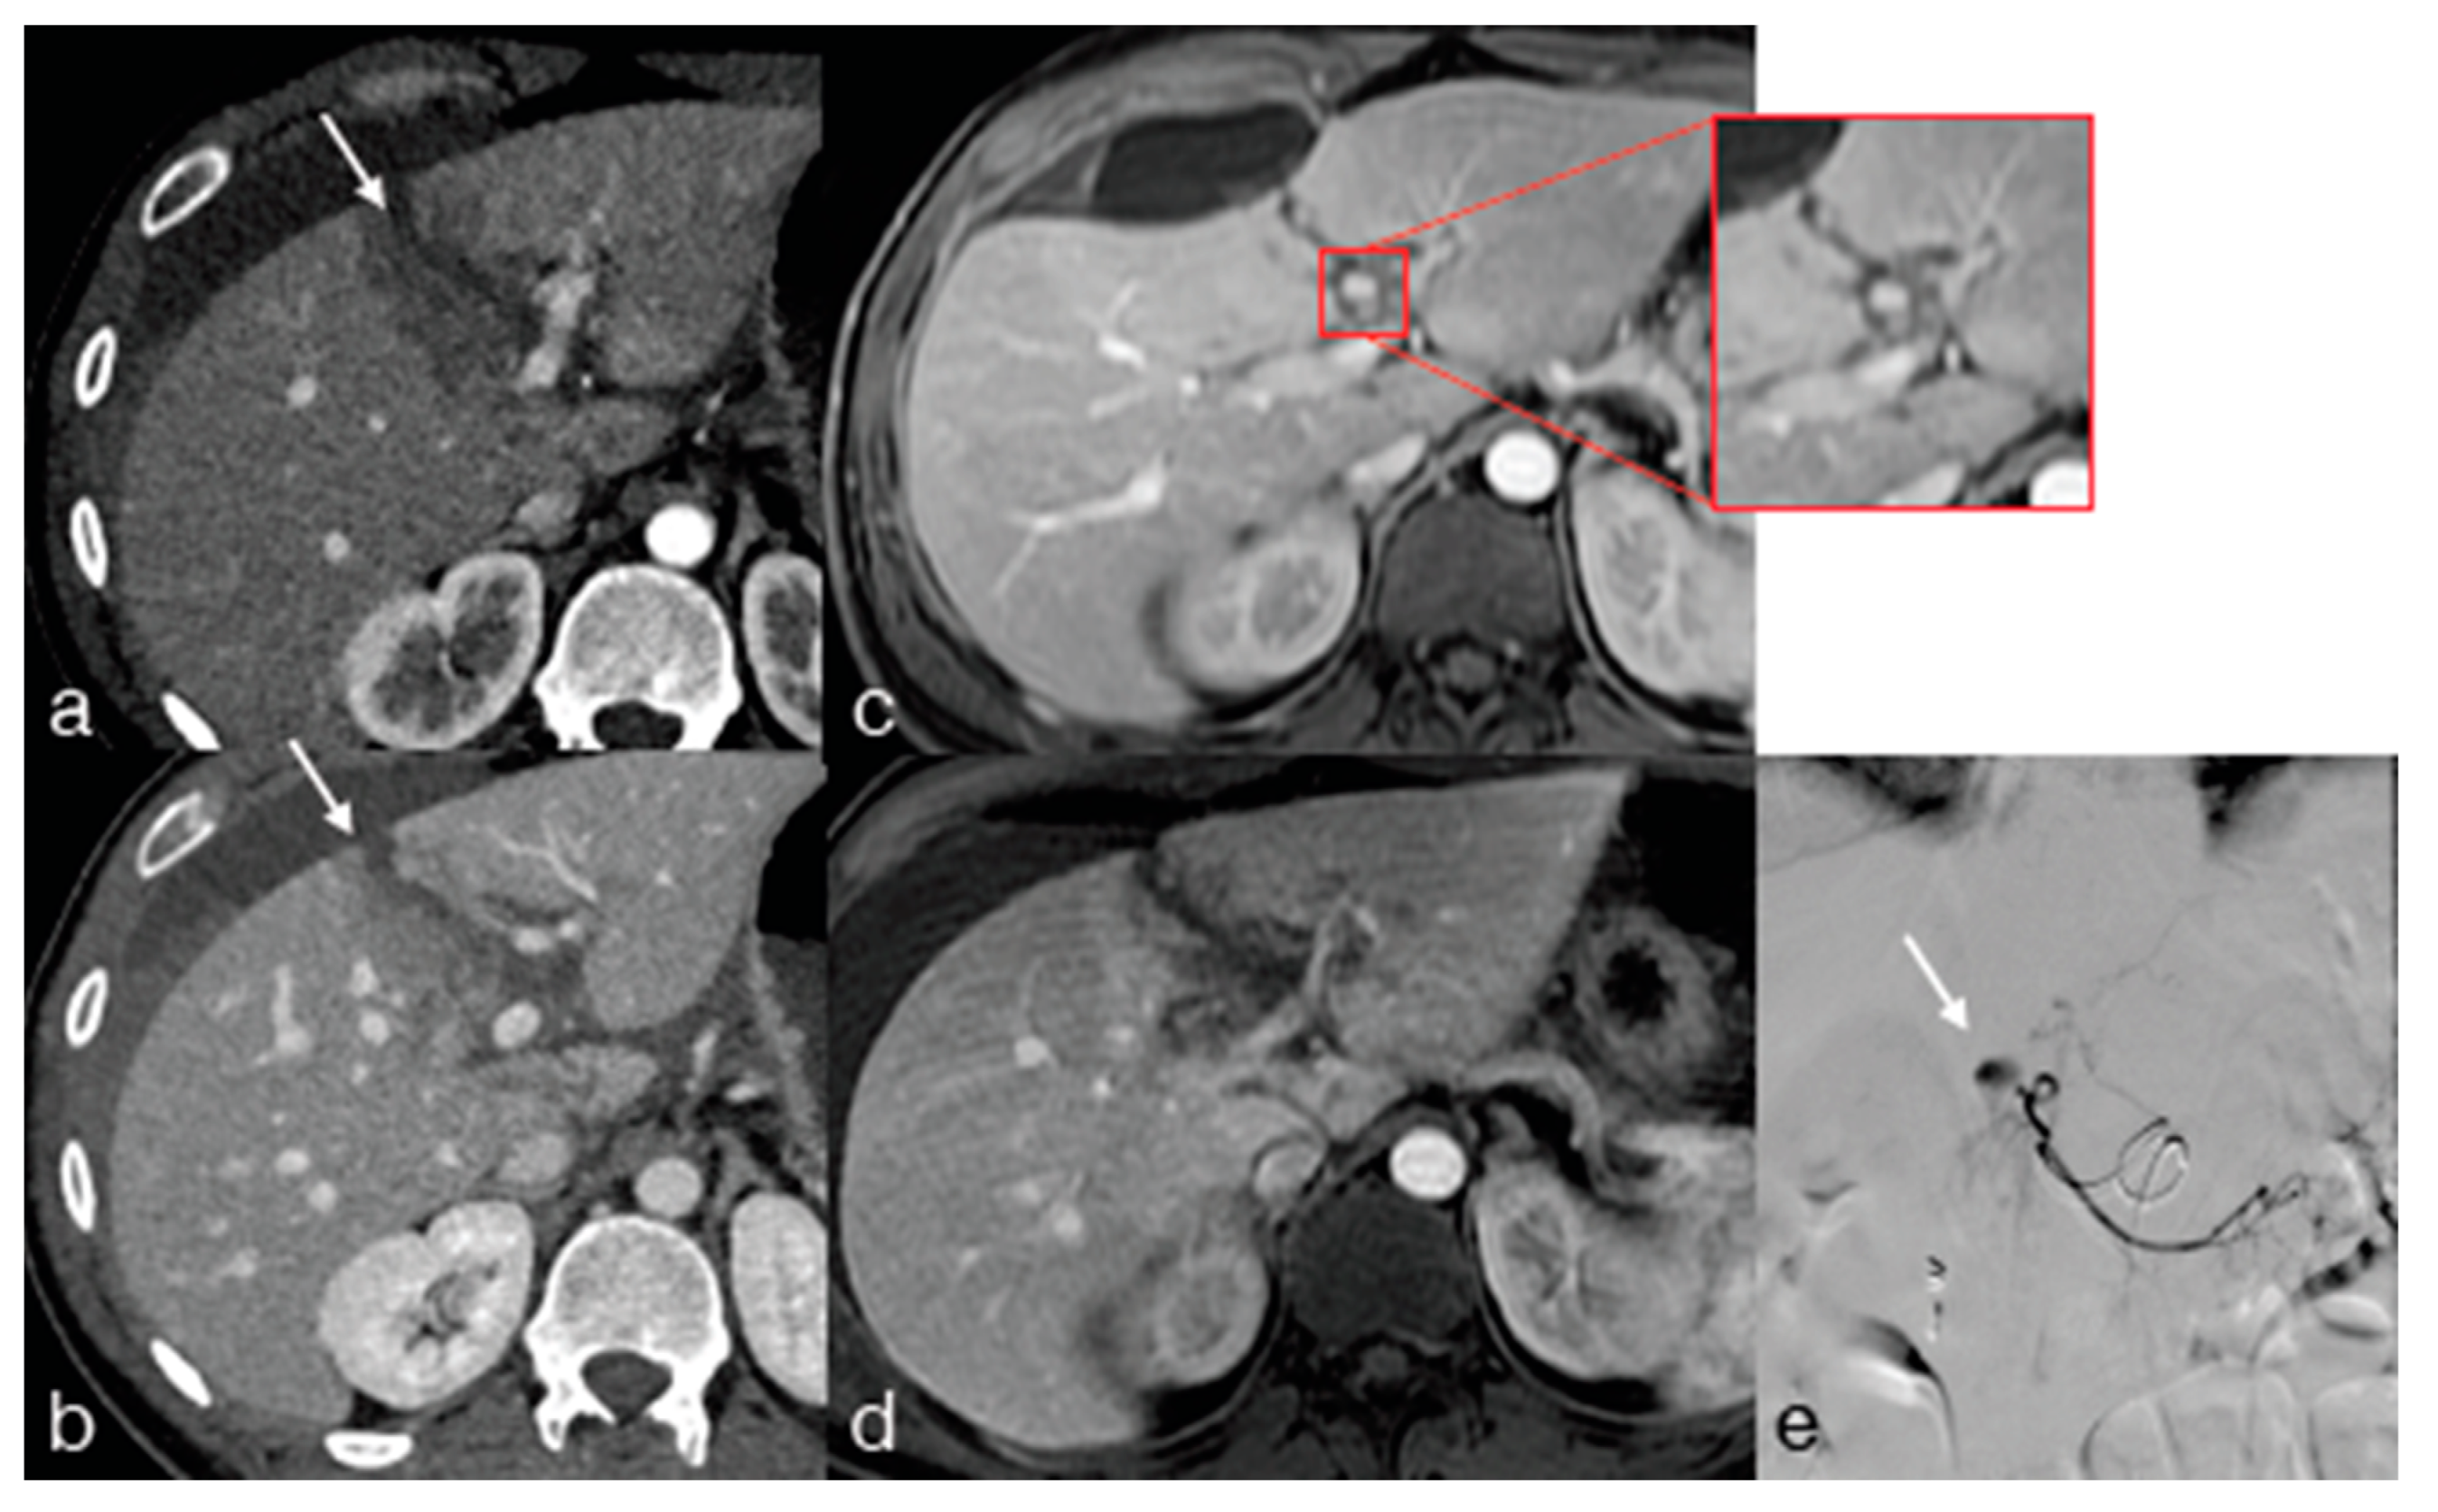

- Iacobellis, F.; Di Serafino, M.; Brillantino, A.; Mottola, A.; Del Giudice, S.; Stavolo, C.; Festa, P.; Patlas, M.N.; Scaglione, M.; Romano, L. Role of MRI in early follow-up of patients with solid organ injuries: How and why we do it? Radiol. Med. 2021, 126, 1328–1334. [Google Scholar] [CrossRef] [PubMed]

- Miele, V.; Piccolo, C.L.; Sessa, B.; Trinci, M.; Galluzzo, M. Comparison between MRI and CEUS in the follow-up of patients with blunt abdominal trauma managed conservatively. Radiol. Med. 2015, 121, 27–37. [Google Scholar] [CrossRef] [PubMed]